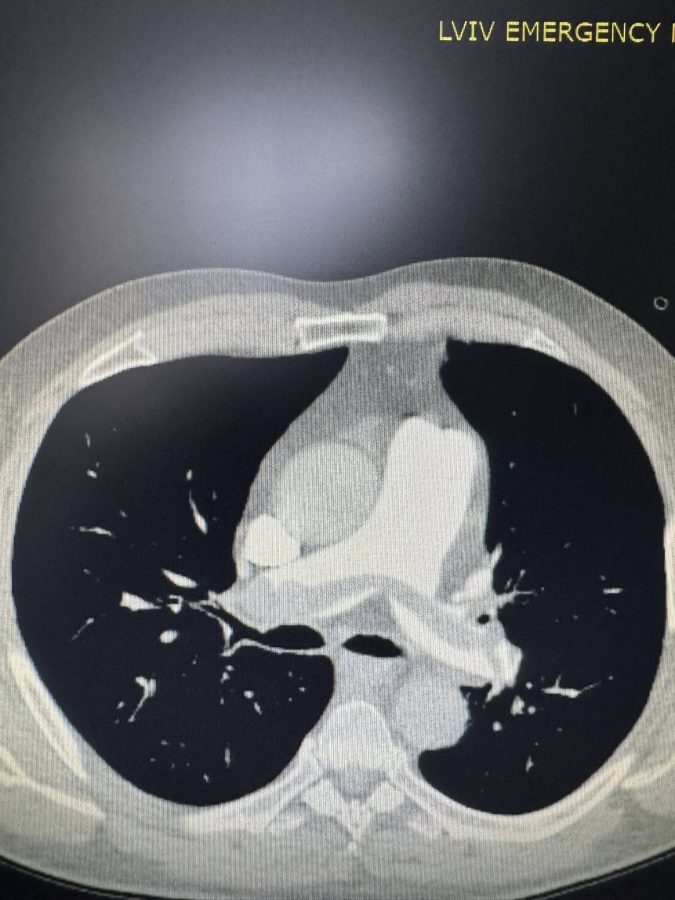

До клініки потрапили двоє пацієнтів із розвитком тромбоемболії легеневої артерії (ТЕЛА) – один цивільний чоловік та військовий, який лікувався після мінно-вибухової травми.

Медики прийняли рішення провести ендоваскулярну операцію під рентгенконтролем: через судини катетером дісталися тромбів і видалили їх спеціальною системою аспірації.